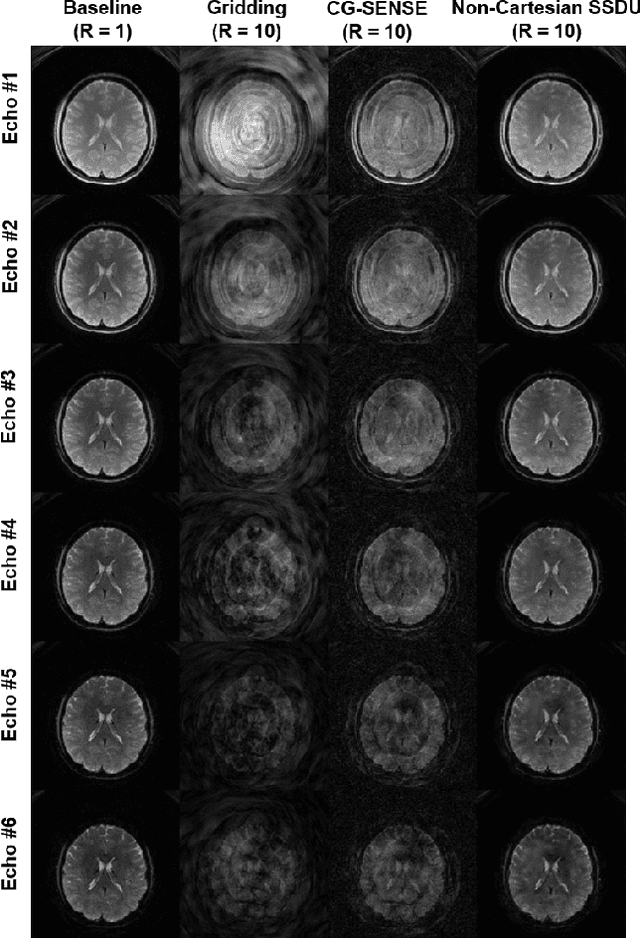

Abstract:Functional MRI (fMRI) is an important tool for non-invasive studies of brain function. Over the past decade, multi-echo fMRI methods that sample multiple echo times has become popular with potential to improve quantification. While these acquisitions are typically performed with Cartesian trajectories, non-Cartesian trajectories, in particular spiral acquisitions, hold promise for denser sampling of echo times. However, such acquisitions require very high acceleration rates for sufficient spatiotemporal resolutions. In this work, we propose to use a physics-driven deep learning (PD-DL) reconstruction to accelerate multi-echo spiral fMRI by 10-fold. We modify a self-supervised learning algorithm for optimized training with non-Cartesian trajectories and use it to train the PD-DL network. Results show that the proposed self-supervised PD-DL reconstruction achieves high spatio-temporal resolution with meaningful BOLD analysis.